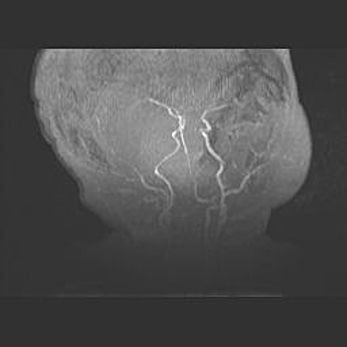

Наружная гидроцефалия с возможной атрофией височных областей.

Возраст: 28 дней

Вес: 3670 г

Пол: мужской

Окружность головы: 38 см

Срок гестации: 40 недель

Гидроцефалия головного мозга у новорожденных – это заболевание, которое характеризуется скоплением избыточного количества спинномозговой жидкости в желудочковой системе головного мозга в результате затруднения её перемещения от места выработки к месту поглощения в кровеносную систему или вследствие нарушения абсорбции. При открытой наружной форме гидроцефалии у новорожденных расширяются и переполняются субарахноидные пространства.

При нормотензивных  формах,  которые,  как  правило,  являются  следствием  перенесенных ишемических  повреждений  паренхимы  мозга,  возможно  сочетание микроцефалии  с нормотензивной гидроцефалией. В основе данных изменений лежит атрофия больших полушарий с преимущественной  локализацией  в  лобно-височных  областях.